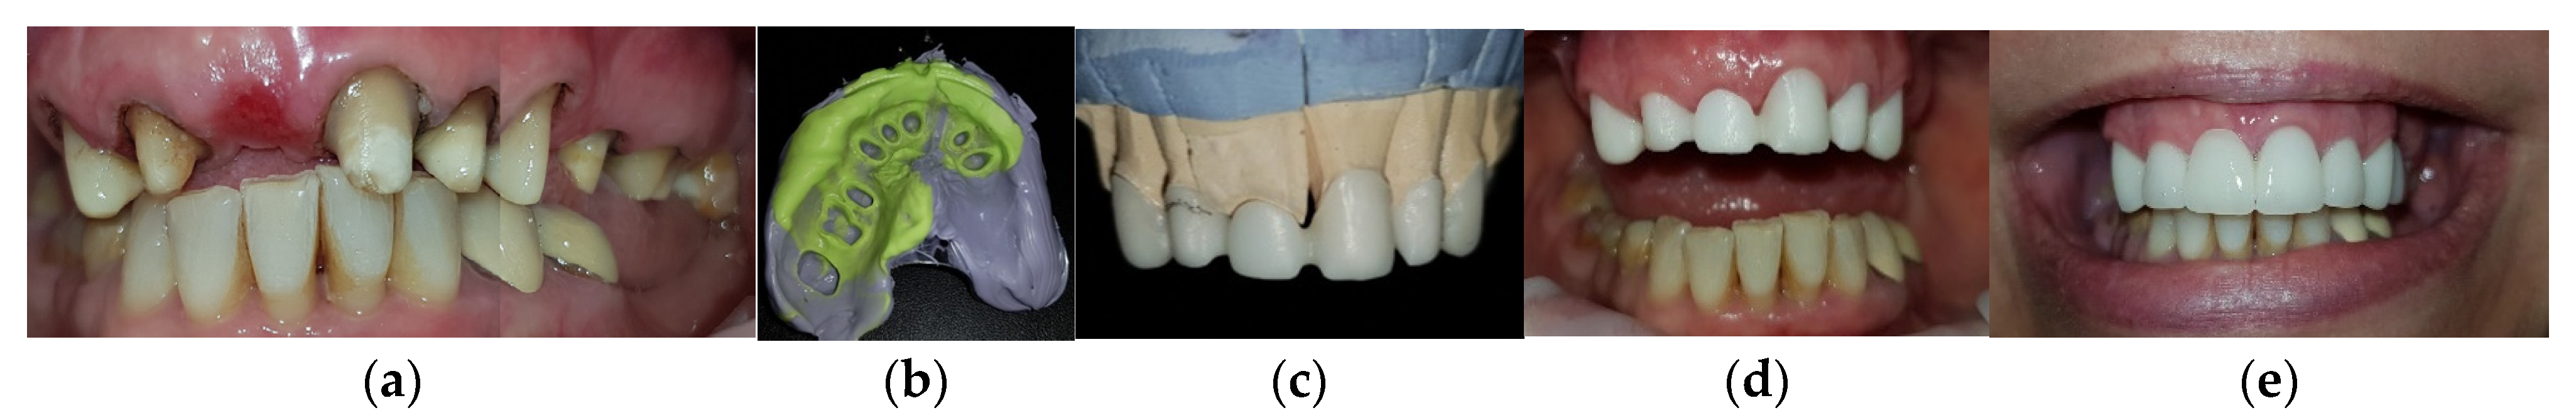

2. Case Report